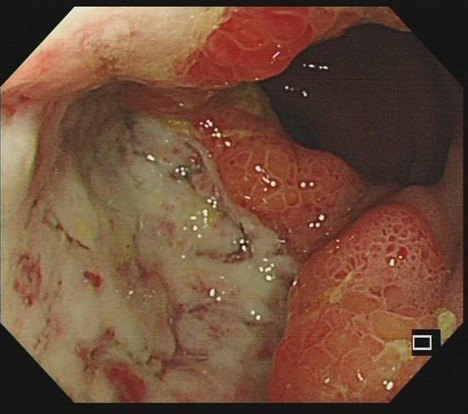

克罗恩病是一种慢性炎症性肠道疾病,对患者的生活造成了极大的困扰。作为一名医生,我经常遇到患者对于不治疗克罗恩病的后果感到担忧。在这里,我将为大家解答这个问题。

克罗恩病会导致腹泻、腹痛、消化不良等严重的肠道症状。如果不进行治疗,这些症状将持续存在,严重影响患者的生活质量。患者可能需要频繁就医,并面临着无法正常工作、学习和社交的困扰。不治疗还可能导致营养吸收不良,引发贫血、体重下降等健康问题。

克罗恩病未经治疗可能会引发一系列并发症。例如,长期的肠道炎症会损害肠道组织,导致肠道狭窄和梗阻。这不仅会加重腹痛和腹泻等症状,还可能引发急性肠梗阻,危及生命。此外,克罗恩病还与其他系统的炎症性疾病如关节炎、皮肤溃疡等相关联,。